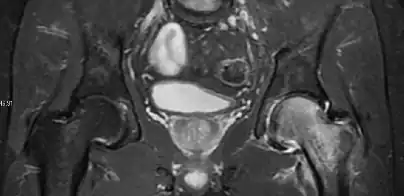

Intra-articular osseous causes of pain include several conditions: avascular necrosis (AVN), transient osteoporosis of the hip (TOH), tumors, and stress or insufficiency fractures. All these entities may present with a pattern of bone marrow edema characterized by decreased signal intensity on T1 weighted images and increased signal intensity on fluid sensitive sequences, such as fat saturated T2-weighted or STIR images. When there is no evidence of a focal lesion associated with the edema pattern, TOH is suspected. When a band of low intensity is seen inside the edematous area, the shape and length of this band become important. It is generally convex to the articular surface in the case of subchondral stress or insufficiency fractures, whereas it is concave, circumscribing all of the necrotic segment, in cases of AVN. When doubts do persist, gadolinium-enhanced MRI tends to show that the proximal portion beyond the band is enhanced in fractures but is not in AVN.[1]

MRI has been shown to have 100% sensitivity and specificity in prospective studies of occult hip fractures. These fractures were diagnosed by bone marrow edema and a low signal fracture line, mainly on T1 or T2 weighted images (Figure 10).[1]